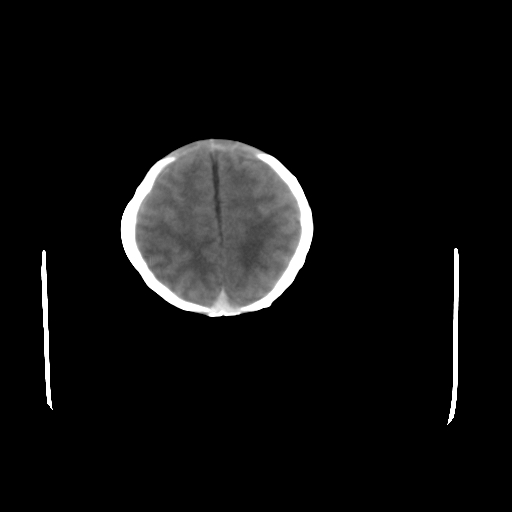

男,12天,自然分娩,其母发现右顶部头皮包块逐渐增大。

疑问:患儿脑白质密度比较低,基底节区密度比较高,类似于“双圈征”脑沟密度也偏高。该婴儿可有别的异常吗?反射正常吗?评分能达到5分吗?如果正常,就随诊观察吧。不正常要考虑到缺血缺氧性脑病。

鉴别:骨膜下血肿,一般为产伤,应用产钳之类的吧